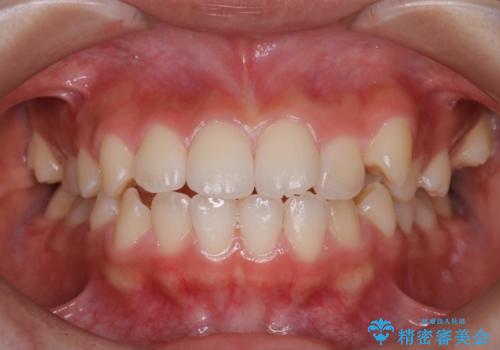

ハーフリンガル 半分裏側矯正による上下前突の抜歯矯正治療

- 20代女性

- 上下左右4本の第1小臼歯を抜歯する、抜歯矯正を計画した。

抜歯矯正により前歯の位置が後ろに下がり、わずかではありますが、口元に改善がみられ、歯並びもきれいに整いました。